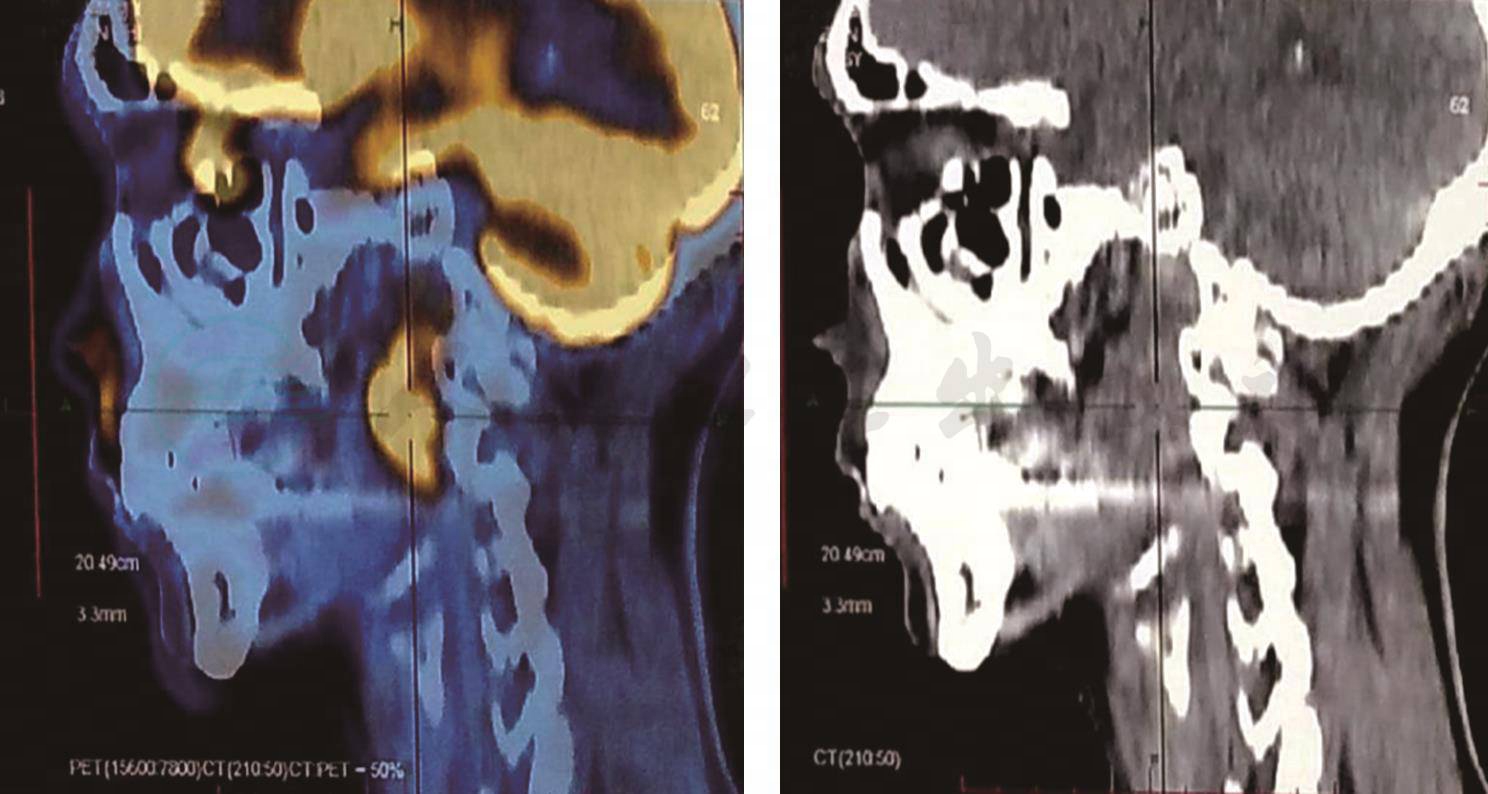

4.PET/CT报告

①鼻咽癌综合治疗后,鼻咽左侧壁软组织肿块,累及颈动脉鞘,向后累及咽后间隙及左颈部Ⅱ区多发代谢增高的淋巴结:鼻咽癌复发并多发淋巴结转移可能性大;②右侧第2前肋骨骨折愈合期改变,患者否认外伤或碰撞史,病理性骨折不排外,请结合临床;③纵隔及双肺门区多发淋巴结、代谢增高:淋巴结转移?反应性增生?建议追踪观察或淋巴结活检以明确;④左肩局部肌肉代谢增高,多为生理性摄取;⑤双侧筛窦炎;⑥肺气肿(右上肺肺大泡形成),右中上肺少量纤维条索灶;⑦右肾结石,双肾多发囊肿,前列腺增生;⑧脊柱退行性改变,L1椎体陈旧性压缩性骨折,S1腰化,双侧骶髂关节炎(图5)。

图5 PET/CT

该患者为鼻咽癌复发,鼻咽左侧壁可见一向后下延伸至咽喉间隙的软组织影,同时累及颈动脉鞘,糖代谢异常浓聚,SUV最大值为11.7,左侧咽后间隙及颈Ⅱ可见多发肿大淋巴结,糖代谢增高,SUV最大值为9.6。从影像科来看,鼻咽癌复发诊断明确。在临床中FDG对肿瘤诊断、分期及疗效评估是很常用的,但需要注意的是,部分肿瘤18FDG PET/CT诊断并不占优势,如前列腺癌、高分化型原发性肝癌。这时可以采用其他的标记物,如11C-胆碱PET/CT。若为神经内分泌肿瘤,则可使用18F-奥曲肽类似物显像。因此在临床中,针对不同疾病选择正确的影像学检查对于正确诊断疾病意义重大。